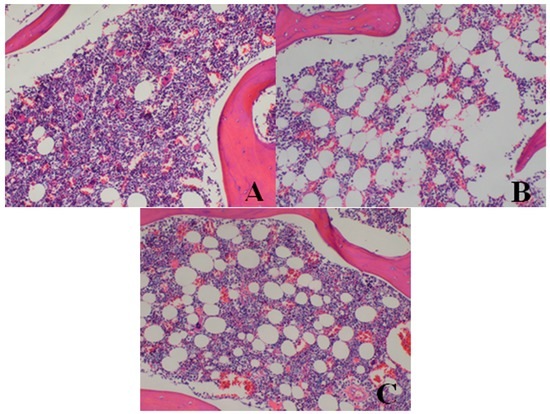

3.1.6. Bone Marrow Examination

3.2.5. Bone Marrow Examination

| Bone marrow of sternum | decrease in hematopoietic cell numbers | 0/4 | 0/4 | 0/4 | 2/4 | 3/4 |